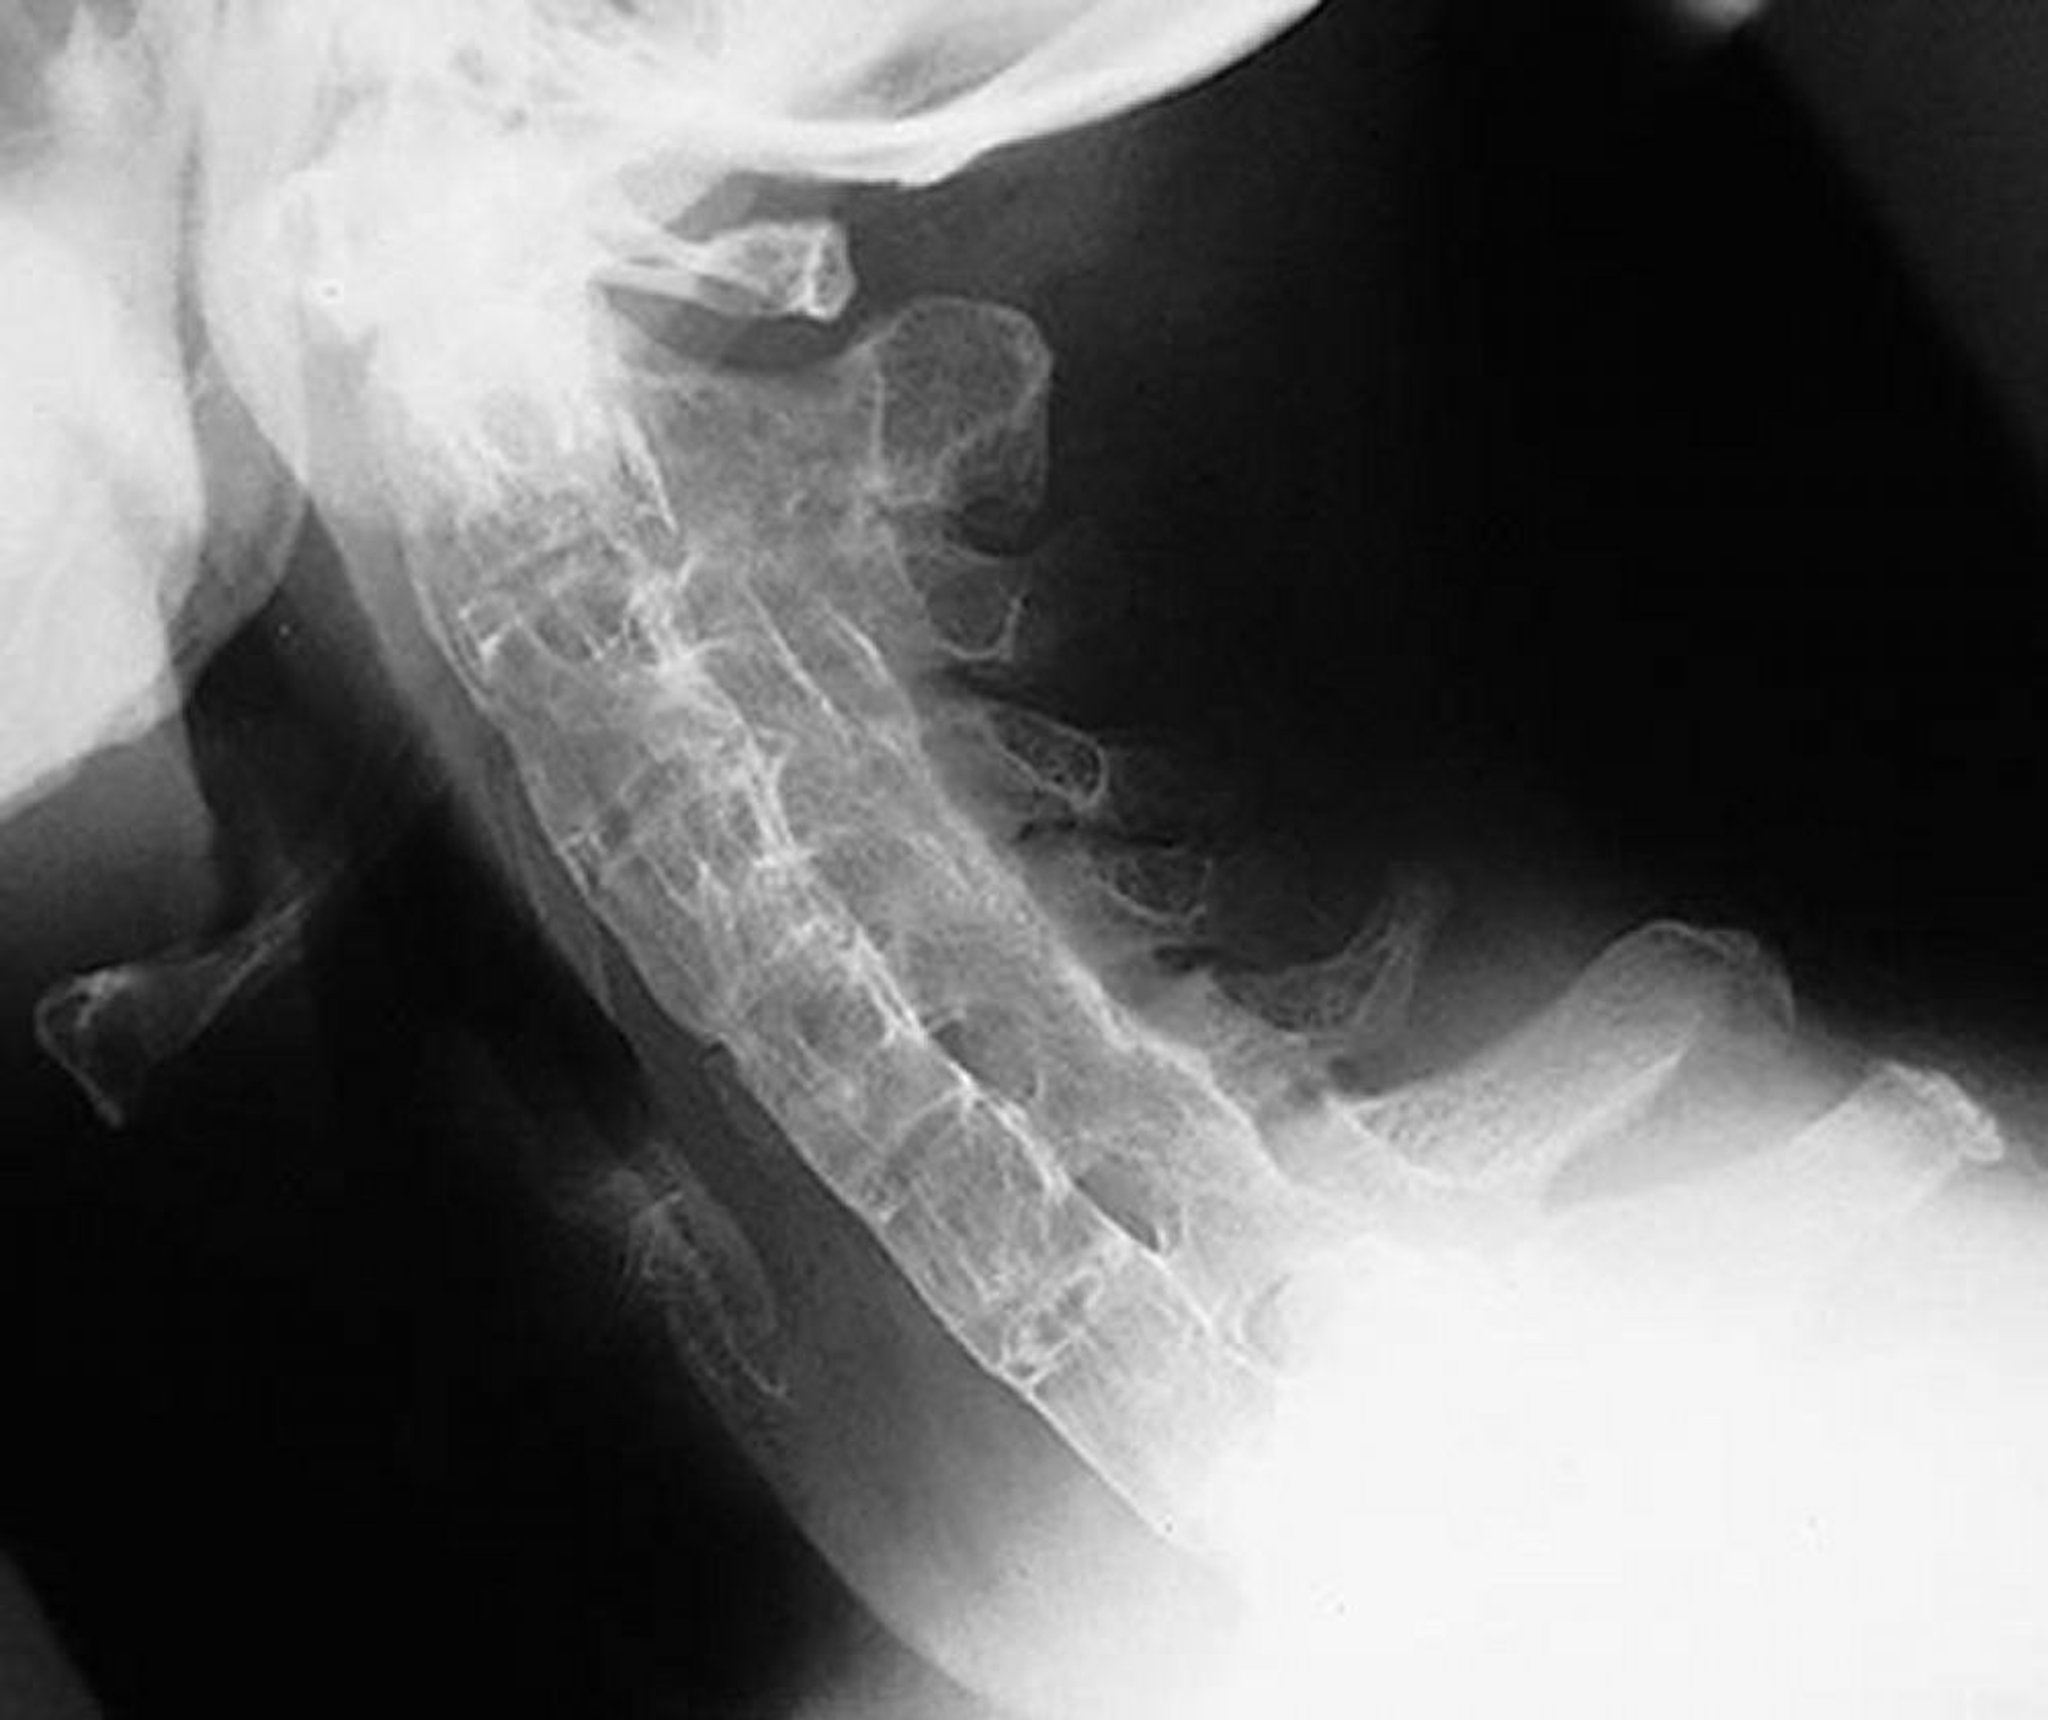

"Бамбуковый позвоночник" при анкилозирующем спондилите

На этом латеральном изображении шейного отдела позвоночника показано окостенение шейного отдела позвоночника у пациента с тяжелым давним анкилозирующим спондилитом. Позвоночник полностью анкилозирован («бамбуковый позвоночник») благодаря синдесмофитам, слитым фасеточным (апофизарным) суставам и параспинальной кальцификации связок.